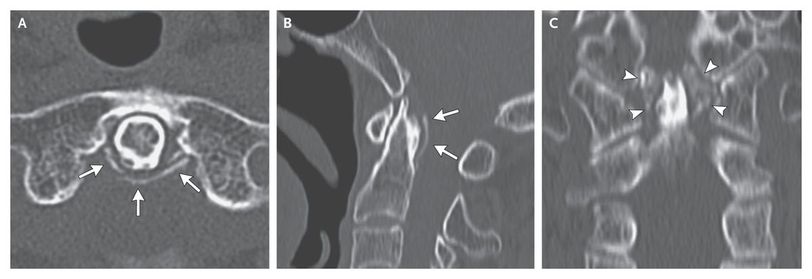

An 88-year-old woman presented with a 2-month history of recurrent episodes of acute pain in her neck and knees that were associated with fevers of 38 to 39.3°C. She reported no visual symptoms, jaw claudication, morning stiffness, or pain in the upper arms or shoulders. Radiography revealed chondrocalcinosis in the knees and stippled calcifications in the pubic symphysis. Computed tomography of the neck showed curvilinear calcifications of the transverse ligament of the atlas (Panel A, arrows), a linear calcification (Panel B, arrows), and crown-shaped calcium deposits surrounding the odontoid process (Panel C, arrowheads). Crowned dens syndrome is characterized by recurrent neck pain related to radiodense deposits of hydroxyapatite or calcium pyrophosphate dihydrate in ligaments around the odontoid process, which create the appearance of a crown or halo surrounding the odontoid process on radiographic imaging. Evidence of inflammation (e.g., fever or elevated levels of C-reactive protein) is typical. A short course of prednisolone (15 mg per day), followed by administration of nonsteroidal anti-inflammatory medication, completely alleviated her symptoms. Long-term treatment with antiinflammatory agents is usually unnecessary in patients with this condition.